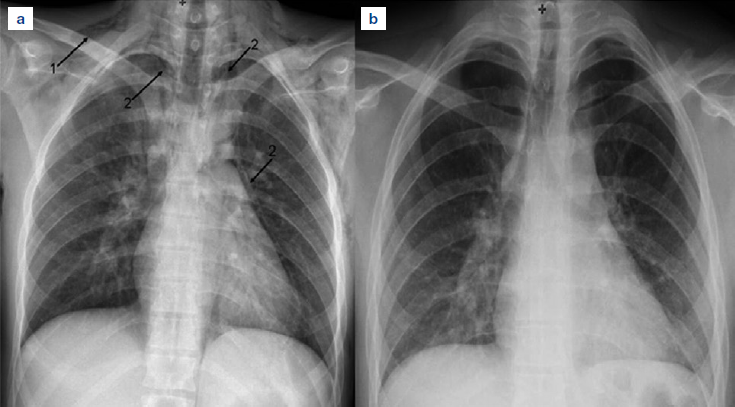

Uomo caucasico di 23 anni, fumatore da 10 anni di circa 20 sigarette al giorno, tossicodipendente dall’età di 16 anni (ultima assunzione di eroina 48 ore prima) e in terapia con metadone, si presentò presso il Pronto Soccorso (PS) del nostro ospedale per la comparsa di vomito alimentare ripetuto, associato a faringodinia, astenia e febbre, in assenza di dolore toracico e tosse. Da segnalare in passato, trauma cranio-facciale 4 anni prima e un non meglio identificato intervento chirurgico nell’infanzia per possibile stenosi pilorica. All’esame fisico il paziente risultò emodinamicamente stabile con parametri vitali nella norma, nulla a carico dell’apparato respiratorio. Gli esami ematochimici evidenziarono leucocitosi neutrofila (14,74 x 103/ml, valori normali 2,00-7,50) e incremento della proteina C reattiva (1,3 mg/dl, valori normali < 0,50 mg/dl). La radiografia standard (Rx) del torace, riscontrò enfisema sottocutaneo a livello dei tessuti molli cervico-toracici e aria libera in sede mediastinica (Figura 1a). A quel punto, dopo valutazione del chirurgo generale e dello pneumologo, si concordò con il medico del PS approfondimento diagnostico: a) la tomografia computerizzata (TC) del torace con mezzo di contrasto idrosolubile per via orale, eseguita immediatamente, ha confermato lo pneumomediastino ed esclusa una perforazione esofagea (Figura 2); b) la fibrobroncoscopia (FBS), eseguita in seconda giornata dopo il ricovero in degenza ordinaria in pneumologia, ha escluso lesioni tracheobronchiali.

Il paziente fu posto in riposo assoluto e trattato con levofloxacina (500 mg 1 compressa al giorno), probiotici e inibitori della pompa protonica (pantoprazolo 40 mg, 1 compressa al giorno); la FBS documentò un quadro endoscopico nella norma e consentì il prelievo di campioni di lavaggio bronchiale per citologia e per esami colturali di germi comuni, miceti e micobatteri, risultati poi tutti nella norma. In terza giornata, l’rx torace evidenziò la riduzione sia dell’enfisema sottocutaneo sia dello pneumomediastino; il paziente fu dimesso in pieno benessere in quinta giornata. L’ultimo controllo radiografico, effettuato dopo undici giorni dall’esordio (Figura 1b), mostrò completa risoluzione di enfisema e pneumomediastino.

Figura 1.a) Radiografia del torace eseguita in Pronto Soccorso dove si evidenzia la presenza di aria libera in sede mediastinica (freccia 2) e presenza di enfisema sottocutaneo (freccia 1). b) Radiografia del torace in XI giornata che evidenzia completa risoluzione del quadro.